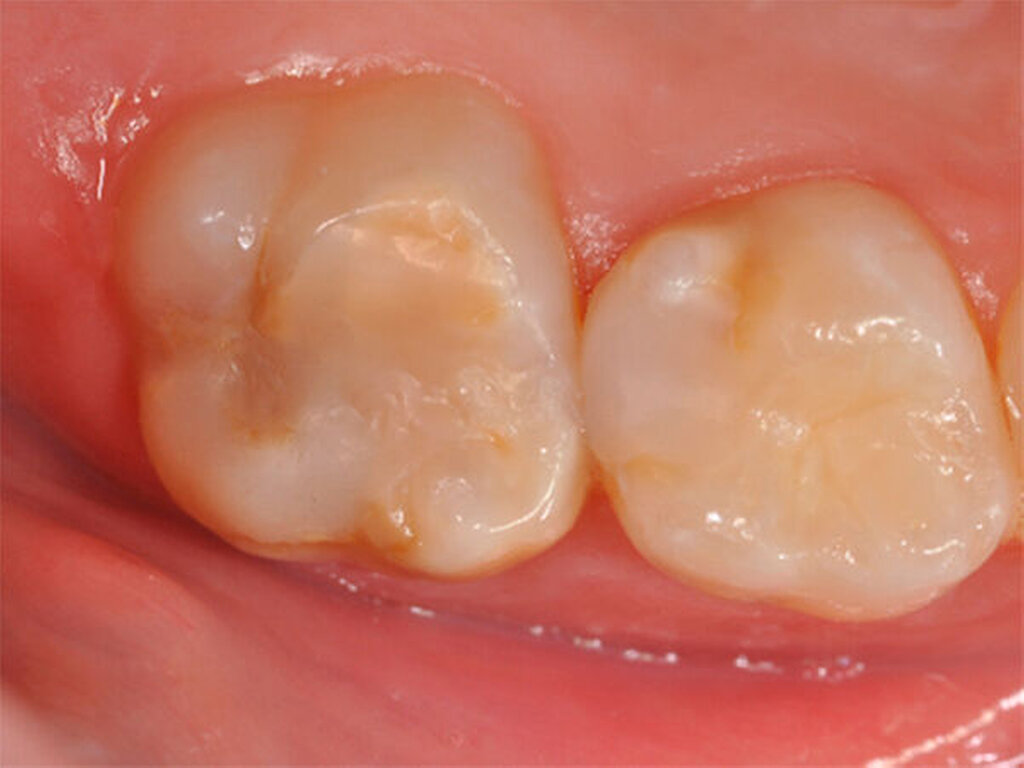

Milde Form der MIH. Verfärbungen, die auf den weichen MIH-Schmelz hinweisen, sind auf der Kaufläche des Backenzahnes zu erkennen. Ein wichtiges Charakteristikum des Schmelzes ist die um Faktor 10 reduzierte Härte, so dass mit Karies und Einbruch der Oberfläche unter Kaubelastung gerechnet werden muss. |

Krämer